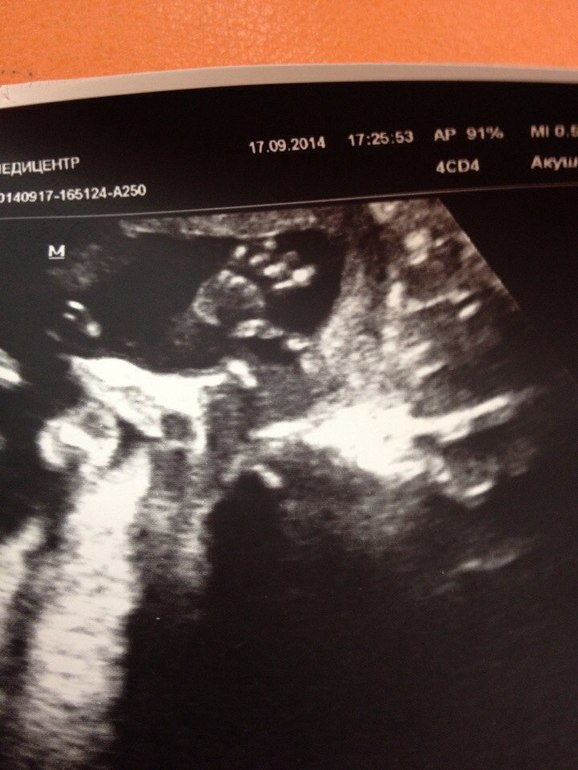

3Д узи в 18,5 (18.6) недель..

Ураааа)))) Сходила в первый в своей жизни раз на 3Д узи, он же и второй скрининг...хотя, на мой взгляд, для скрининга рановато..

Это круто, конечно)))) Когда включался эффект 3Д, датчик вибрировал и было щекотно)))) Василиса девушка скромная у нас, закрывала личико двумя руками, так что видили мы только попку и ручки))))) Опережает срок на 1 день, что можно скинуть на разность аппаратов, ПДР поставили на 12 февраля, а было 13... Сказали, что девочка длинноногая, длиннорукая и длиннопальцая

))))))))И тенденция к крупному плоду))))) Знаем, проходили)))) Личико не показала, зато "привет" всем передала)))) Ловите: